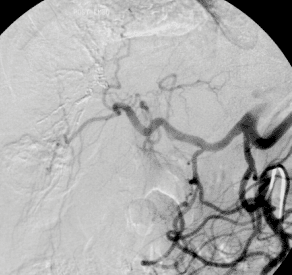

Technik

Der:die Patient:in erhält zunächst ein Schmerz- und Beruhigungsmittel, unter Umständen ist auch eine Vollnarkose möglich. Nun wird ein Katheter an der rechten Seite des Halses in eine Vene eingeführt und weiter in Richtung Leber geschoben. Dieser Katheter dient zum Einführen aller notwendigen Geräte für die Anlage des TIPS. Von der rechten Lebervene aus wird innerhalb der Leber (intrahepatisch) mit einer Punktionsnadel eine Verbindung zur Pfortader gestochen. An einem eingelegten Führungsdraht entlang wird dann diese Öffnung mit einem Ballon geweitet und dann eine Metallgeflechtprothese (Stent) eingeschoben. Diese Röhre aus Metallmaschen soll den neu geschaffenen Abfluss offen halten. Nun wird mehrmals der Druck im Pfortadersystem gemessen. Das Ziel ist einen Shunt mit einem Durchmesser zu erzielen, bei dem genau die für den:die Patient:in richtige Blutmenge durch den Shunt abfließt, bei der kein Stau mehr entsteht, aber auch noch möglichst viel Blut durch die Leber fließen und dort entgiftet werden kann.

© Universitätsklinik für Radiologie und Nuklearmedizin

Abbildung 1: TIPS vor und nach erfolgreicher Anlage

Ist ein TIPS eingesetzt, so kann es vorkommen, dass sich mit der Zeit die Durchblutung wieder verschlechtert. In solchen Fällen muss eine Neueinstellung des TIPS vorgenommen werden. Ist der Leberumgehungskreislauf zu klein, besteht weiterhin die Gefahr von Blutungen aus den Krampfadern der Speiseröhre. Eine „Stentverkleinerung“ ergibt sich im Krankheitsverlauf häufig durch zunehmendes Gewebswachstum in oder an den Rändern des Stents, weshalb regelmäßige Kontrollen im Rahmen der Nachsorge äußerst wichtig sind! Gegebenenfalls ist eine erneute angiographische Untersuchung mit Aufdehnung des Stents notwendig.